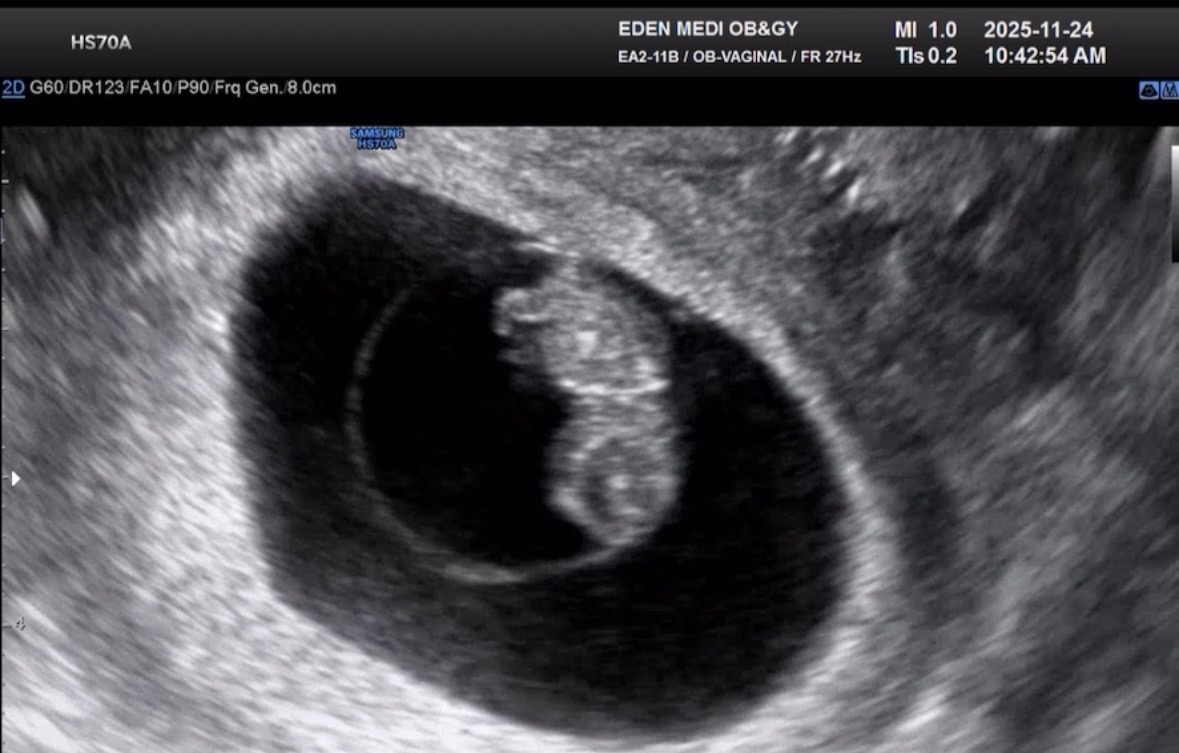

와 8주인데 벌써 애기 모양이 있어요 와 ㅎㅎ 아고 귀여웡 ㅎㅎ

8주 젤리곰

37세 결혼 1년만에 찾아온 아기. 첫 임신이라 모든게 신기허고 노산이라 불안도 하고 그와즁에 너무 귀엽고 그러네용!!